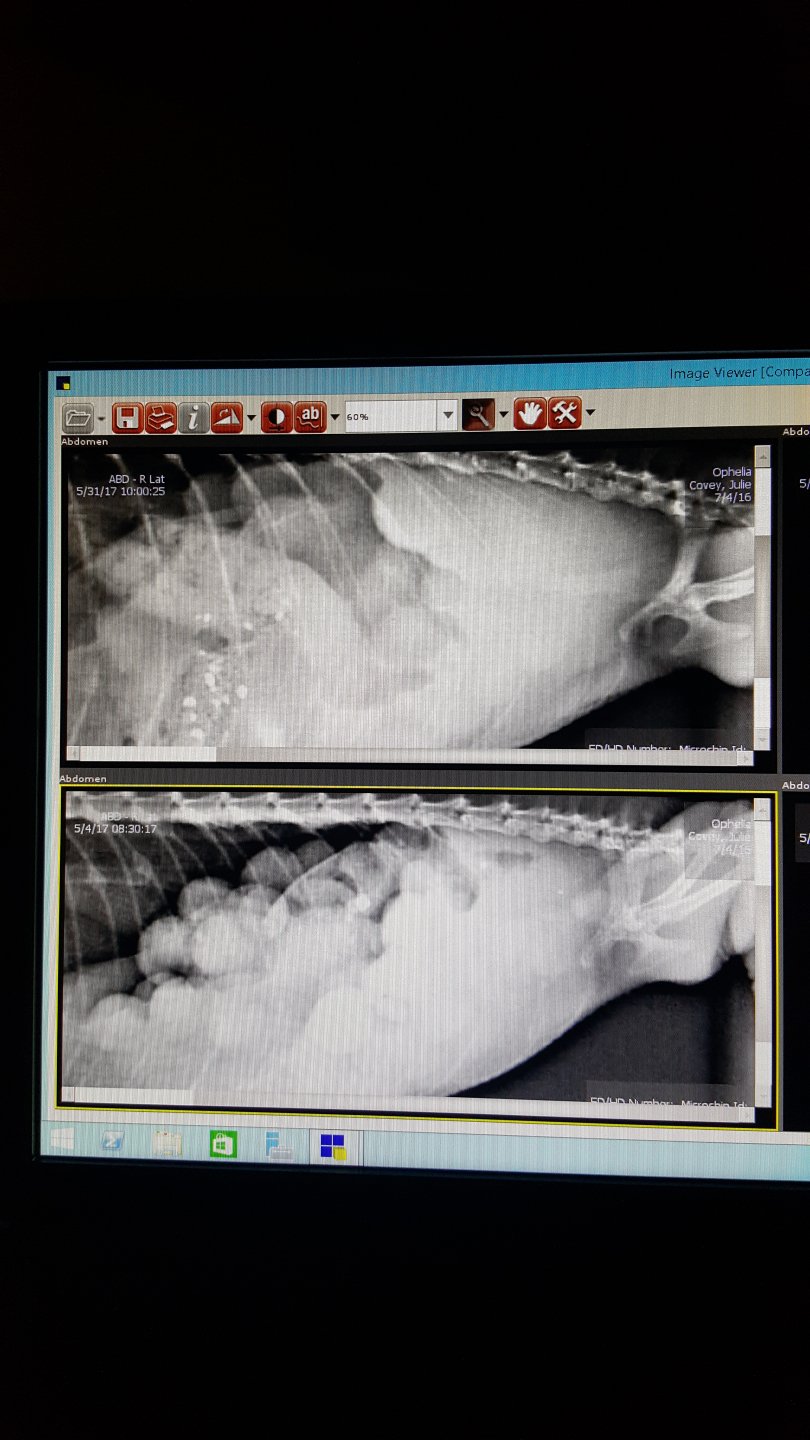

For reference and comparison, he took xrays to see what changes had occurred. Pictures below. He said that there has not been much change. There has not been any shell/calcification made to the eggs/follicles... her belly is still soft.